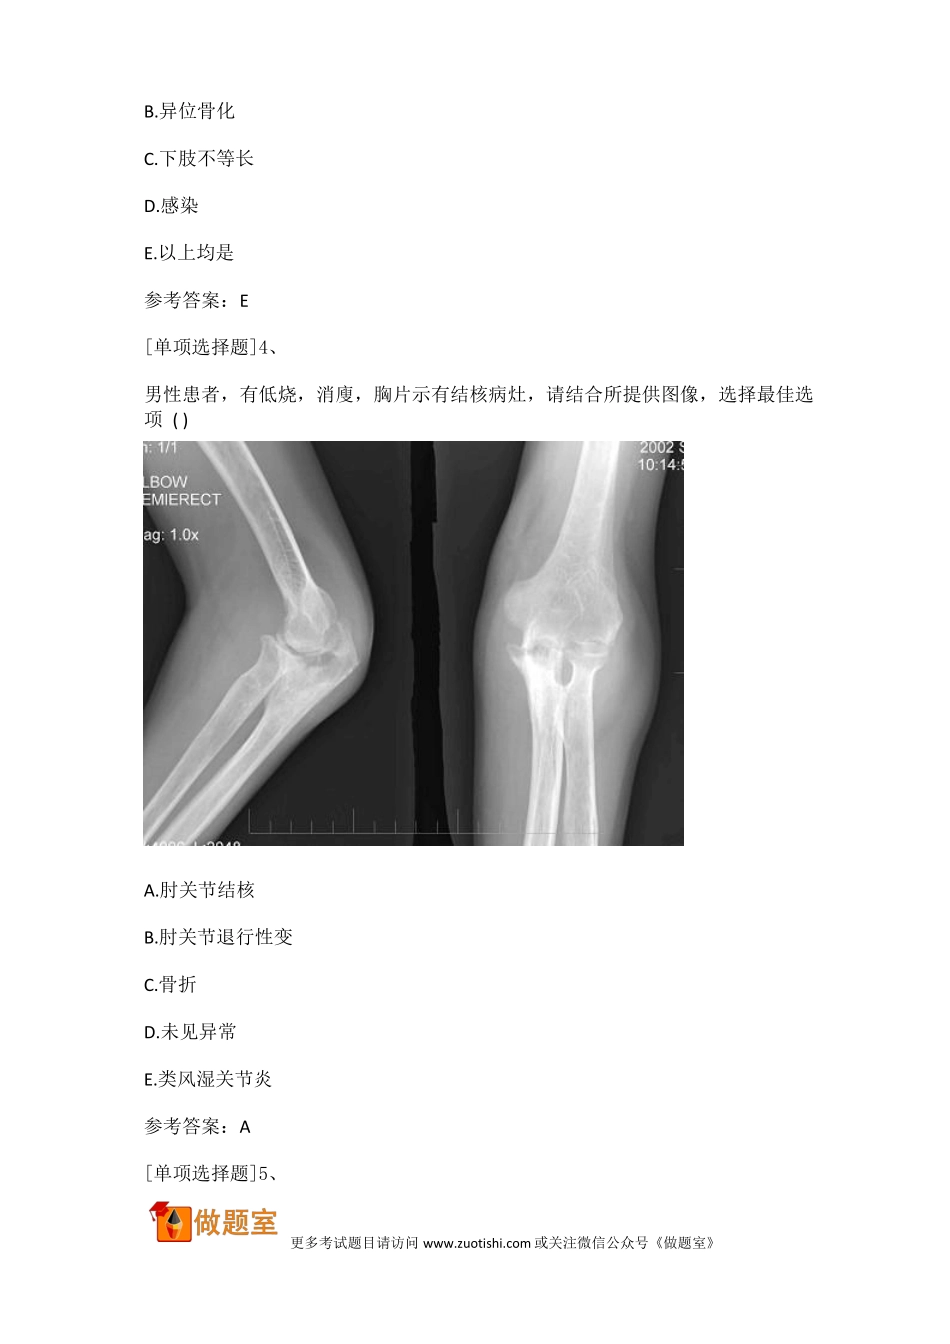

2018 年骨外科学副主任医师真题精选(副高)[单项选择题]1、男,7 岁,外伤致肱骨髁上伸直型骨折,经手法复位、石膏外固定,6 小时后出现手的感觉麻木,主动活动障碍,此时应当立即采取A.拆除石膏,改用骨牵引治疗B.手术治疗C.密切观察,暂不做任何处理D.臂丛麻醉E.血管扩张剂参考答案:A参考解析:肱骨髁上伸直型骨折出现手的感觉麻木、主动活动障碍,原因可能是石膏过紧压迫肱动脉所致,应立即拆除压迫原因,改用骨牵引治疗,密切观察患肢情况,视情况再决定进一步处理措施。故选 A。[单项选择题]2、下肢骨折引起整个肢体极度外旋位时,最可能的损伤是A.股骨颈骨折B.股骨转子间骨折C.股骨干骨折D.股骨髁上骨折E.髋关节中心型脱位参考答案:B[单项选择题]3、人工全髋关节置换术可出现的术后并发症是A.关节假体脱位更多考试题目请访问 www.zuotishi.com 或关注微信公众号《做题室》B.异位骨化C.下肢不等长D.感染E.以上均是参考答案:E[单项选择题]4、男性患者,有低烧,消廋,胸片示有结核病灶,请结合所提供图像,选择最佳选项 ( )A.肘关节结核B.肘关节退行性变C.骨折D.未见异常E.类风湿关节炎参考答案:A[单项选择题]5、更多考试题目请访问 www.zuotishi.com 或关注微信公众号《做题室》